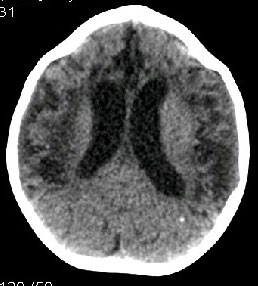

女,2岁。生后以来智力低下,长期易感冒,发烧,身体差。孕史,用药史不详!

三脑室、侧脑室扩大,脑沟裂增宽明显,尤以大脑半球为甚。胼胝体压部及膝部狭小便薄。考虑1脑小畸形

2脑萎缩[发育不全所致可能或hie]

双侧大脑大部分半球虫蚀样密度减低,脑实质呈负占位效应,脑室扩大,低密度边缘散在钙化影阴,长期易感冒,发烧,身体差,请详细询问有无发热时的抽搐病史。我觉得像是:脑炎后遗症。

本例特点:1 脑室扩大.以三脑室,四脑室扩大为主.2 脑沟 脑裂增宽,以纵裂增宽为主.3 脑实质内大量低密度影,(提示缺血及脱髓鞘变性).4 双侧顶枕部点状钙化.

结合临床考虑:1 神经皮肤综合征_结节性硬化.2 胼胝体发育不良.

2岁智低体弱女婴脑部ct平扫示

额、颞、顶叶

皮质变薄(脑沟裂增宽)伴灶性梗死(小灶脑脊液样低密度影)、

白质减少(脑室增大)并变性(脱髓鞘所致的较对称分布的灶性近似脑脊液密度的低密度灶,个别与脑室穿通)、

颞枕叶交界脑质近凸面点索样钙化灶

考虑多为

化脑后遗改变(脑萎缩、灶性脑软化形成)

——婴幼儿脑组织尚处于继续发育阶段,单纯说脑萎缩不确切,我觉得说脑萎缩伴发育不良更好些。

这种脑萎缩及脑软化灶形成不可逆转,所以此婴预后不良。

鉴别:1、重度hie后遗改变 hie一般不会出现点索样钙化灶;

2、结脑后遗改变 结脑出现钙化的机会更多,呈斑片状,且往往在脑底部,脑质改变往往不如脑室改变(交通性脑积水)更显著